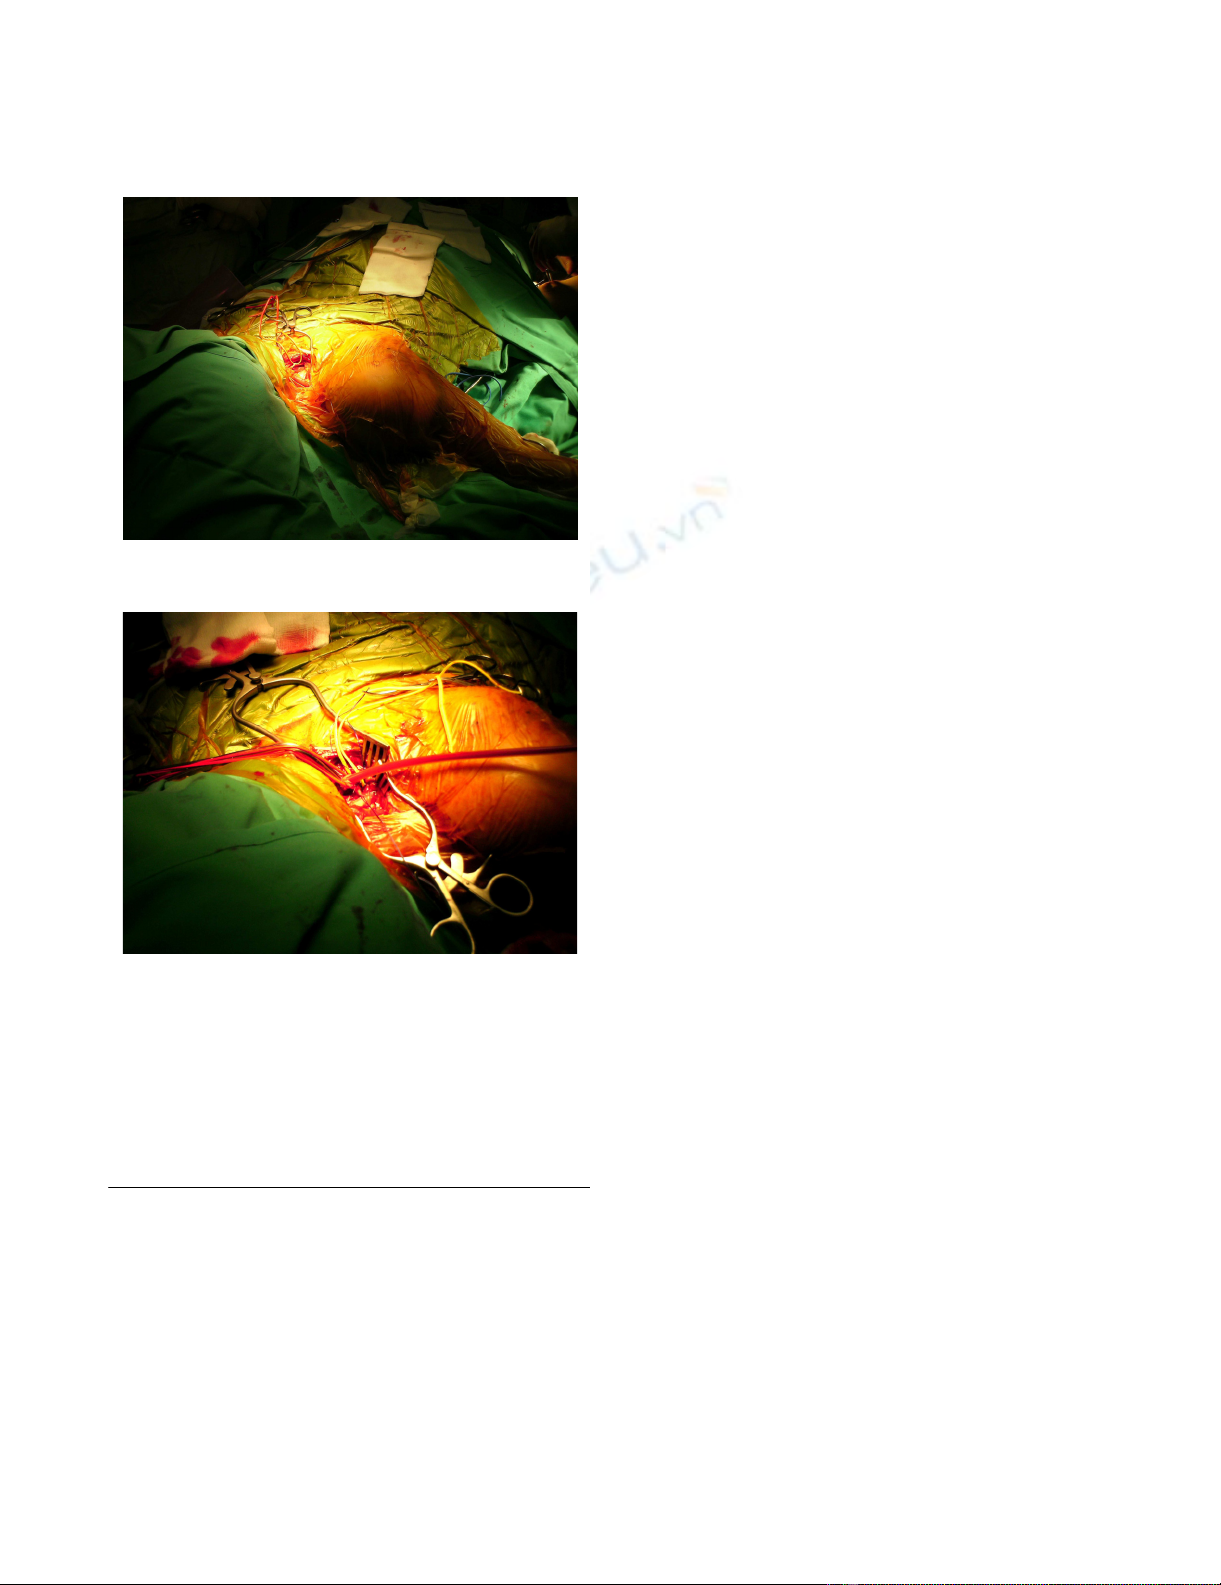

Operative treatment was undertaken with initial exposure

and control of the subclavian artery above the clavicle

(Fig. 3A). Simultaneous exposure of the brachial artery in

Supraclavicular exposure of the subclavian arteryFigure 3

Supraclavicular exposure of the subclavian artery. (A)

The phrenic nerve is retracted before the division of the sca-

lenus anterior muscle. (B) The subclavian artery is exposed

and ligated distally, with blood flow to the right arm being

maintained with the aid of a Javid shunt during open reduc-

tion and internal fixation of the fracture.

(A)

(B)